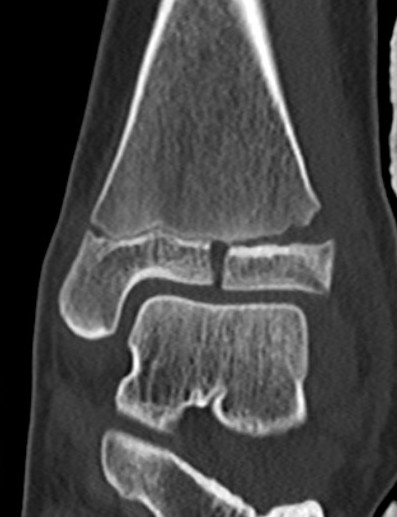

Triplanar Fracture

Definition

Fracture in coronal, sagittal and transverse planes

- crosses epiphysis

- passes through growth plate

- extends into metaphysis

Xray

AP xray: Salter-Harris type III / Tillaux

Lateral xray: Salter-Harris Type II

CT

Coronal images: Salter-Harris type III

Sagittal images: Salter-Harris type II

Axial images: 3 point star